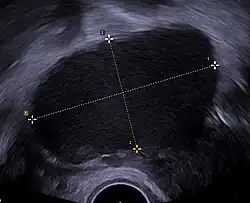

Ultrasound

Vaginal ultrasound can be used to diagnose endometriosis or to localize an endometrioma before surgery. It can be used to identify the spread of disease in individuals with well-established clinical suspicion of endometriosis. Vaginal ultrasound is inexpensive, easily accessible, has no contraindications, and requires no preparation.[30] By extending the ultrasound assessment into the posterior and anterior pelvic compartments, a sonographer can evaluate structural mobility and look for deep infiltrating endometriotic nodules.[31]

Ultrasounds cannot be used to exclude a diagnosis of endometriosis.[32] If a transvaginal ultrasound is not suitable or declined, an alternative is an ultrasound via the lower abdomen.[33]